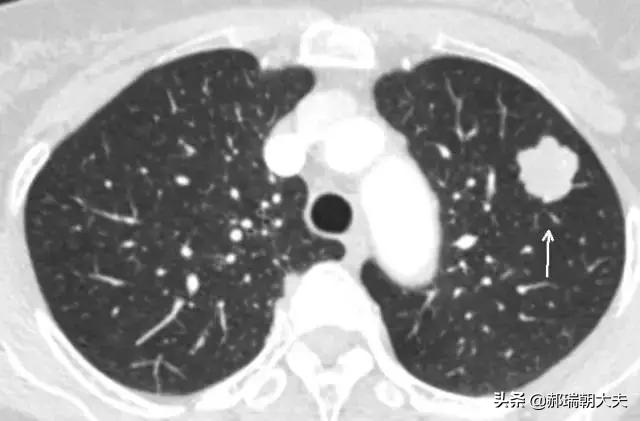

Les examens médicaux étant de plus en plus fréquents, les nodules pulmonaires sont de plus en plus souvent détectés. Les nodules pulmonaires sont un terme d'imagerie, et la définition d'imagerie d'un nodule pulmonaire est une petite lésion bien définie qui est complètement entourée par le parenchyme pulmonaire (Diamètre ≤30mm). La morphologie des nodules est classée comme solide ou sub-solide ; les nodules sub-solides sont eux-mêmes classés en nodules de verre dépoli et en nodules partiellement solides. Les lésions de plus de 30 mm de diamètre sont des masses plutôt que des nodules et ont une probabilité plus élevée d'être malignes.

La définition actuellement acceptée d'un nodule pulmonaire est une ombre pulmonaire focale, arrondie, hyperdense, solide ou subsolide, d'un diamètre ≤3 cm. Ces dernières années, avec l'augmentation de la population examinée par tomodensitométrie à faible dose, la proportion de nodules pulmonaires multiples détectés en plus des nodules pulmonaires isolés a considérablement augmenté. Les nodules pulmonaires multiples se présentent souvent sous la forme d'un nodule pulmonaire unique accompagné d'un ou plusieurs petits nodules. Les nodules pulmonaires multiples sont définis comme 2 lésions ou plus. Les patients présentant des nodules pulmonaires multiples peuvent avoir plusieurs sources de cancer du poumon précoce ou de lésions précancéreuses confirmées chirurgicalement et nécessitant une attention clinique particulière.

Nodules pulmonaires : Il s'agit de lésions qui apparaissent dans les tissus des poumons. Il s'agit de lésions arrondies ou irrégulières d'un diamètre inférieur ou égal à 30 mm, souvent entourées de tissu pulmonaire normal. Sur l'imagerie médicale, ils sont décrits comme des "ombres hyperdenses dans les poumons". Les nodules pulmonaires peuvent être uniques ou multiples, avec des limites claires ou floues.

En fonction de l'uniformité de la densité des nodules, on peut les classer en nodules substantiels, en nodules de verre dépoli purs et en nodules de verre dépoli mixtes.